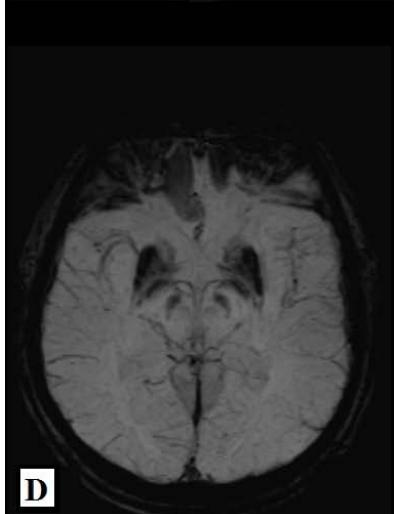

We report a rare case of Wilson’s Disease with neurologic features in a 31-year-old man. This disease consists of a disturbance of copper metabolism secondary to a mutation in the gene responsible for encoding the tissue transporter and the enzyme that incorporates the excess element into bile, generating toxic accumulation in the liver, cornea, and central nervous system. According to his wife, the patient had been treated for an unspecified mood disorder. The clinical picture was characterized by depressive mood, anhedonia, and anxiety. He had his first seizure episode on December 3rd, 2021. He progressed with dysarthria, ataxic gait, dystonia of the right-hand flexor muscles, and intermittent urinary incontinence. Marked worsening was observed after the diagnosis of COVID-19 in February 2022. At the clinical evaluation on March 24th, risorius muscle dystonia (risus sardonicus), resting tremor, and Kayser Fleischer rings at slit-lamp examination was also noted.